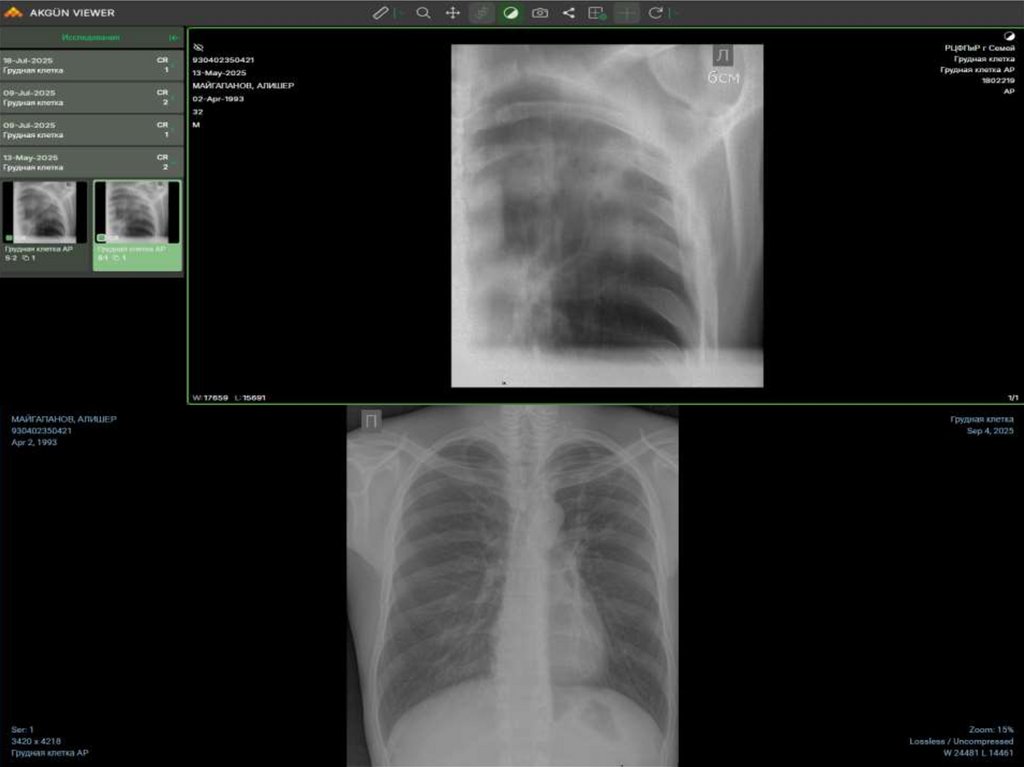

• Дошкова Александра

Николаевна

• 07.11.1993

• Инфильтративный

туберкулез верхних

долей легких в фазе

распада и

обсеменения МТ(+)

ЛЧТБ НС обращение

I категория

• I А группа ДУ.

• Рентгенография ОГК

от 17.12.2024г в

начале лечения

18. Дошкова Александра Николаевна 07.11.1993 Инфильтративный туберкулез верхних долей легких в фазе распада и обсеменения МТ(+)

ЛЧТБ НС

обращение I категория

I А группа ДУ.

КТ ОГК от 19.12.2024 в